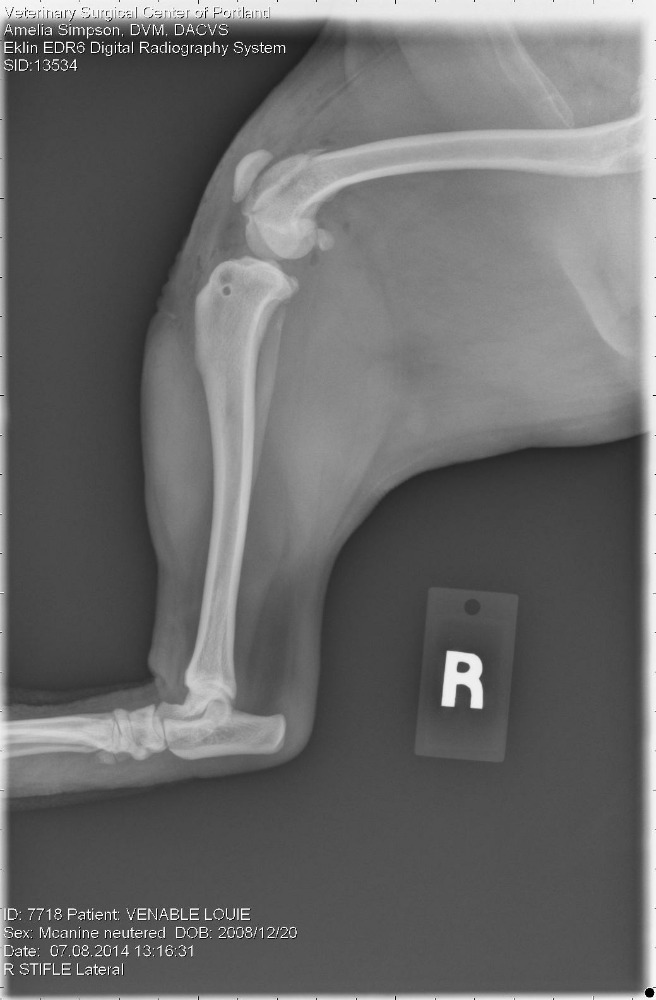

Fundraiser by Ptown N Louie Louie's Double Knee Surgery Dog Double Knee Surgery Dogs rupturing their cranial and caudal cruciate ligament (ccl) causes lameness in their rear legs, often. The signs that made me suspect he. To accomplish this, a veterinary surgeon changes the angle (level) of the joint surface (tibial plateau) by cutting into the tibia bone (osteotomy) and repositioning the resulting bone segment. Does your dog need acl surgery? I’ll detail. Dog Double Knee Surgery.